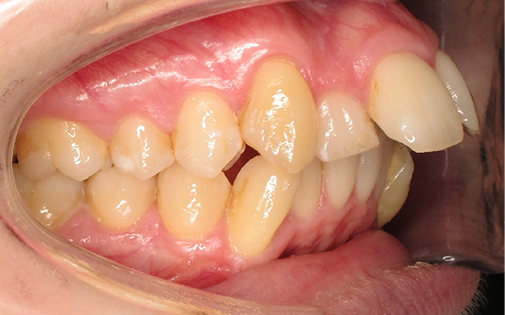

This teenage patient had a very crowded top left canine tooth as well as an underbite. He was successfully treated with Invisalign clear aligners in 22 months.